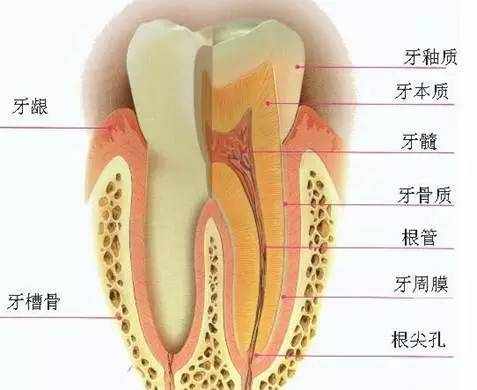

什么是根管?

根管是牙齿硬组织内部的空腔,空腔里的软组织就是牙髓,它包括牙神经、血管、淋巴等组织。

牙髓神经的主要功能是感知冷、热等刺激,并且为牙冠部牙本质等提供营养。在牙齿萌出后,它对于牙齿的功能和健康并非不可或缺。没有牙髓的牙齿仍然可以行使功能。

什么是根管?

根管是牙齿硬组织内部的空腔,空腔里的软组织就是牙髓,它包括牙神经、血管、淋巴等组织。

牙髓神经的主要功能是感知冷、热等刺激,并且为牙冠部牙本质等提供营养。在牙齿萌出后,它对于牙齿的功能和健康并非不可或缺。没有牙髓的牙齿仍然可以行使功能。